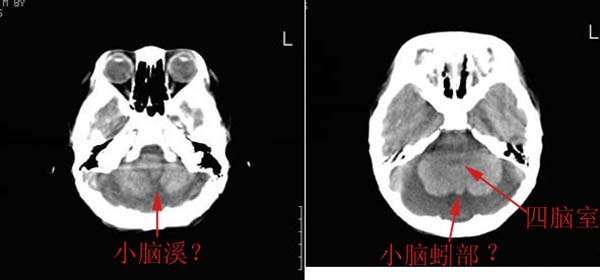

以下是引用wxy7406在2006-12-5 21:02:00的发言:[br]后颅窝囊性低密度灶,双侧小脑半球缩小,蚓部几乎缺失,考虑dandy-walker畸形,建议mri明确。

以下是引用阿圣在2006-12-5 20:55:00的发言:[br]后颅窝囊性低密度灶,双侧小脑半球缩小,蚓部几乎缺失,考虑dandy-walker畸形,建议mri明确